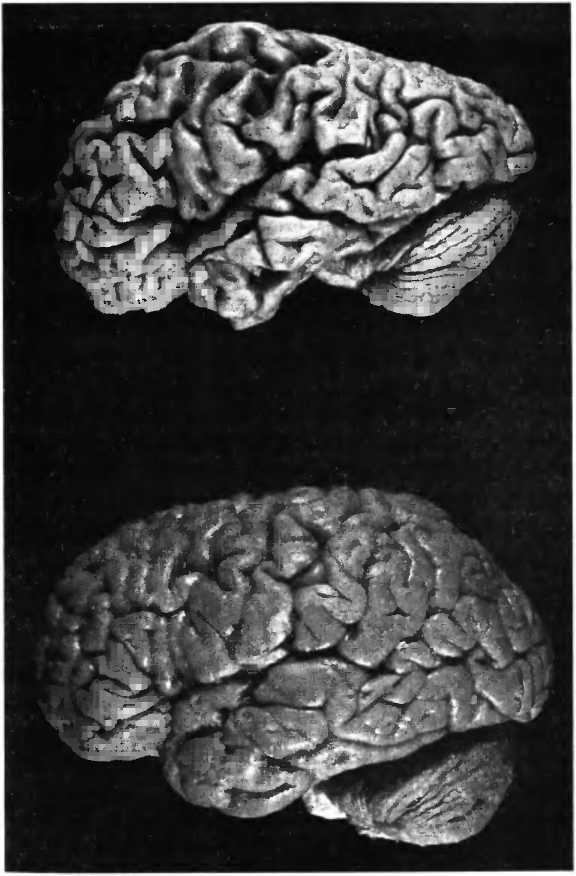

Несмотря на часто сильное сморщивание мозга при болезни Альцгеймера (рис. 31), так что он становится похож на грецкий орех, общее число нейронов в его структуре не уменьшается. Вопреки распространенному мнению, массовой гибели нервных клеток во всем мозге не происходит. Смерть клеток ограничивается пределами нескольких областей мозга: энторинальной коры, части гиппокампа и голубого пятна (locus coeruleus) — и наступает довольно поздно, тогда как снижение активности и поэтому сморщивание нервных клеток (рис. 32) можно наблюдать по всему мозгу уже на ранних стадиях болезни. Этим объясняется тот факт, что в начале болезни ее симптомы могут быть подвержены значительным колебаниям. В какой-то момент у человека могут резко проявиться симптомы деменции, но после этого он вновь оказывается в состоянии поддерживать разговор на обычном уровне. Если бы причиной нарушений памяти на ранней стадии болезни действительно являлась смерть клеток, то никакие колебания симптоматики не возникали бы. Смерть клетки необратима. Еще до того как возникают первые нарушения памяти, измерения показывают уменьшение в мозге глюкозообмена. Внутривенное вливание глюкозы или инсулина улучшает когнитивные способности и указывает на то, что нарушение обмена веществ в мозге является фактором, ограничивающим функциональные способности пациентов.

Рис. 31. При болезни Альцгеймера часто наблюдается сильное сморщивание (атрофия) мозга, он становится похож на грецкий орех. Внизу — здоровый мозг.